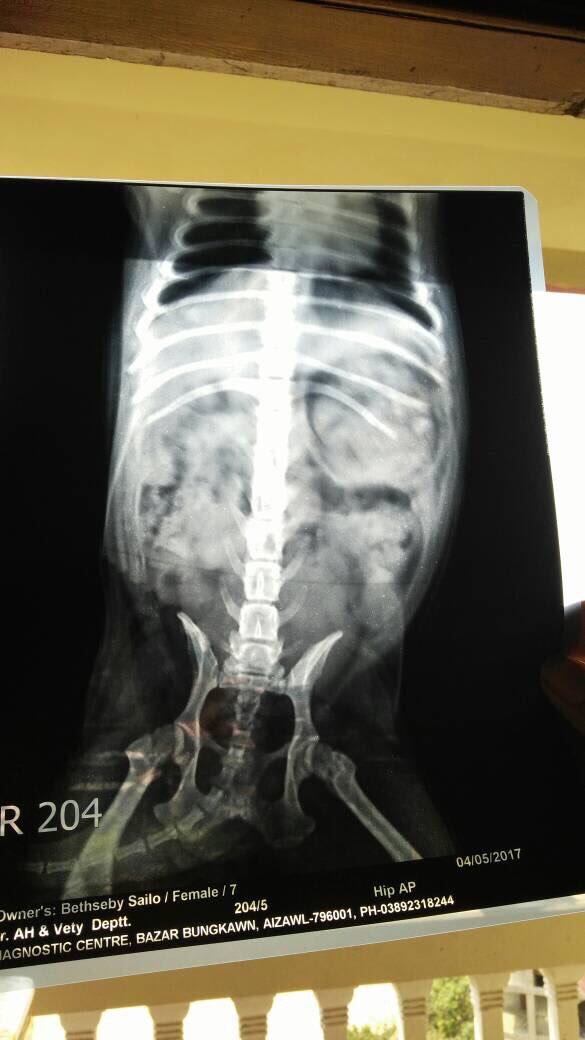

Pet's info: Dog | Pug | Female | unspayed | 7 years old | 19.8 lbs

My pug (F,6yr old) is unlable to walk due to her hind limb.She started limping a little bit since Sepember 2016 and it got worse as she could climb up on the bed or stairs, so this year march, we did an xray, right after which she stopped walking. She could not walk, and one vet says she has hip dysplasia and the other vet says it may be disc prolapse. I dont know what to believe as in a small town like ours, we cannot do ct scan nor mri for dogs hence its very difficult to diagnose.Pls help

I would recommend referral to an orthopedic or neurology specialist in order to correctly determine the underlying cause and to establish a management program going forward to maintain her mobility in the future; the longer this goes untreated the greater chance of permanent changes that may not respond to treatment. Weight management, antiinflammatory medications and diets specifically formulated for joint health and mobility (royal canin mobility / hills joint care) are recommended and acupuncture or chiropractic care may also help with the symptoms